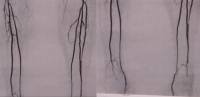

Exemplo de vídeo: DAOP estágio IIb perna direita com estenose subtotal da artéria ilíaca externa, oclusão da artéria femoral comum, oclusão da origem profunda, oclusão de longo segmento da artéria femoral superficial, oclusão da artéria tibial anterior em ambos os lados (direita proximal, esquerda periférica) -> TASC D

PM 320-1

PM 320-2

Zum Vergrößern bitte anklicken